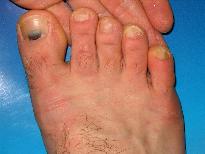

Foto 10. Pacient 25 de ani, internat pt etilism acut. La examenul fizic se evidentiaza onocomicoza incipenta dg. V ambe picioara si marci traumatice (hematoame subunghiale) la halucele drept si dg. III picior sting. Anamneza amanuntita si aplicarea chestionarelor incadreaza pacientul in clasa dependentilor cronici de alcool. |